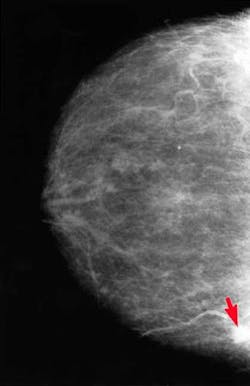

Mammography (digital mammography)On a mammogram, fat in the breast looks dark and the denser breast and connective tissues look light gray or white. Because cancer can also appear white on a mammogram, it is harder to interpret mammograms in women with dense breasts. Standard mammography produces an X-ray image on film, while digital mammography allows the image to be viewed on a computer screen. On the computer, certain sections of the X-ray image can be magnified and easily examined more closely, and the contrast of the image can be adjusted. This makes digital mammography better at finding tumors in women with dense breasts than standard film mammography.(24) Magnetic resonance imaging (MRI), in combination with mammography, is under study as a breast cancer screening tool for women with dense breasts.(25-26) Currently, the American Cancer Society (ACS) feels there is not enough evidence to recommend for or against MRI plus mammography screening for women with dense breasts. Rather, ACS suggests women with dense breasts talk to their health care providers about whether they should consider adding MRI to their annual mammography screening.(25) Ultrasound, in combination with mammography, is also under study as a breast cancer screening tool for women with dense breasts.(26) What if you have dense breasts?

Breast tumor on mammogram (indicated in photo above by red arrow)One last comment, about hereditary breast cancer. Hereditary breast and ovarian cancer seems to have an earlier onset with each generation. Younger age at diagnosis in subsequent generations of BRCA carriers indicates the importance of early breast screening.Women who carry BRCA1 and BRCA2 mutations have elevated lifetime prevalence of breast and ovarian malignancies.(30) In an analysis conducted at one large U.S. cancer center, 303 women from 106 families with deleterious BRCA mutations in two or more generations were identified. All women had breast or ovarian cancer; age at diagnosis was compared between generations. Median age at diagnosis of breast or ovarian cancer was 48 years (range, 23–70) in the older generation and 42 years (range, 20–86) in the younger generation.In summary, there is much information available on breast cancer. Educate yourself for your sake, and that of your patients.References